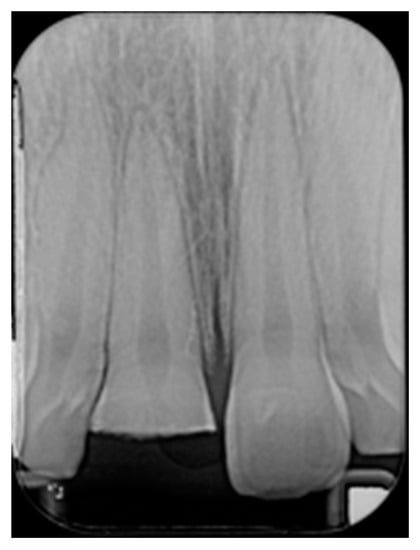

Figure 2.

Initial x-ray. Reprinted from Restauri diretti nei settori anteriori, G. Paolone, S. Scolavino, © 2021, with permission from Quintessence Publishing Italy.